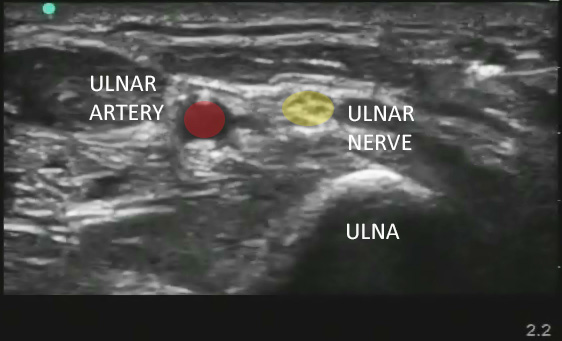

- The ulnar nerve runs down the forearm ulnar (medial) to the ulnar artery.

- In the forearm it lies in the same neurovascular fascia layer as the ulnar artery.

- At the level of the wrist, it is nearly adjacent to the artery.

- In the proximal forearm there is a greater separation between the ulnar artery and nerve.

- Directly medial (ulnar side) to the ulnar artery should be a hyperechoic structure representing the ulnar nerve.

- The nerve can be oval or triangular.

- The ulnar nerve sits in the same echogenic fascial plane as the artery.

Figure 1. Sonographic appearance of the ulnar nerve in the mid forearm